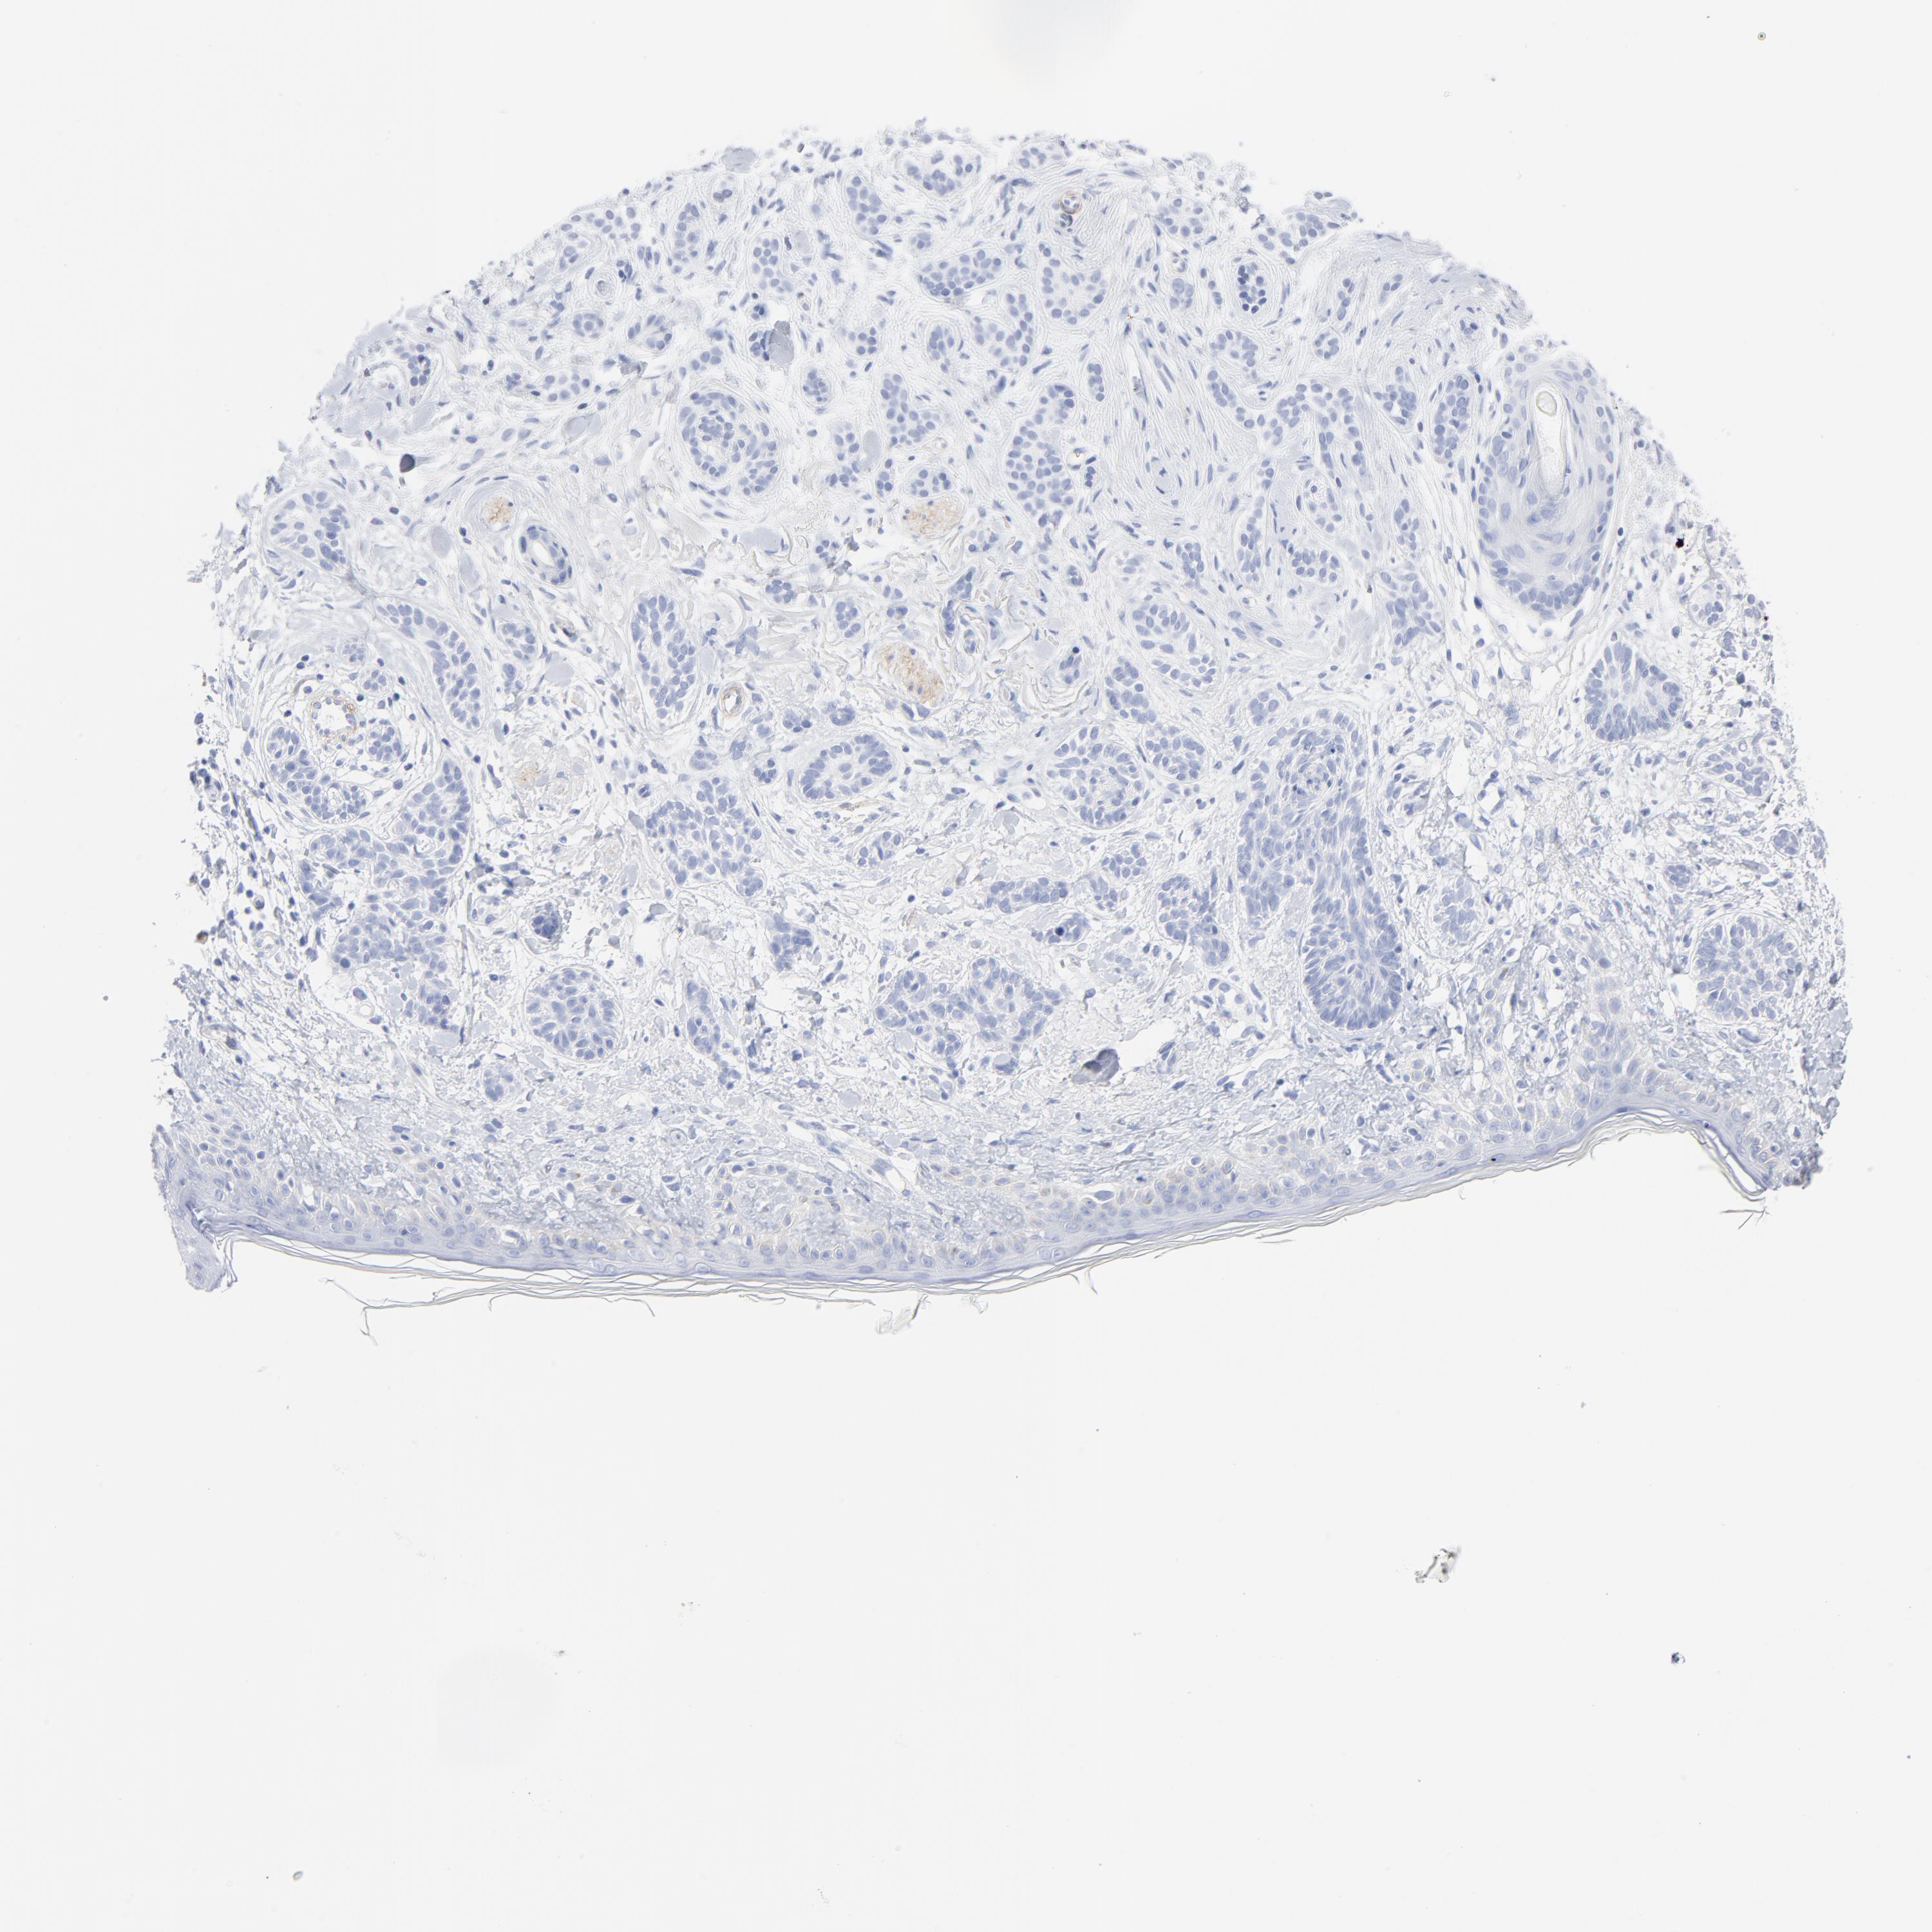

SKIN CANCER - Protein expressioni

A mouse-over function shows sample information and annotation data. Click on an image to view it in a full screen mode. Samples can be filtered based on level of antibody staining by selecting one or several of the following categories: high, medium, low and not detected. The assay and annotation is described here.

Antibody stainingi

Antibody staining in the annotated cell types in the current human tissue is reported as not detected, low, medium, or high, based on conventional immunohistochemistry profiling in selected tissues. This score is based on the combination of the staining intensity and fraction of stained cells.

Each image is clickable and will lead to virtual microscopy that enables deeper exploration of all samples and also displays staining intensity scores, fraction scores and subcellular localization as well as patient and tissue information for each sample.

Antibody HPA003596

Squamous cell carcinoma, NOS

Basal cell carcinoma